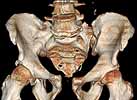

Patient was prone for procedure, as I thought too difficult to fix the wing in lateral position. Of course the repair of wing was easy, but reduction of SI very demanding. The Floro images document the residual lack of reduction. That was the closest I could get it using 6mm joystick in wing, and clamp on sacrum and clamp through notch.  The fixation was (initially) rigid. Anterior ex fix with supra-acetabular pins was placed due to condition of soft tissues, massive "beer-belly" overhanging the crest.

5. Your caudal iliosacral screw is/was in his spinal canal...it's low and posterior and the lateral fluoro image confirms this...a postop CT will show it (or it's trail at this point)...canal screws do not hold.